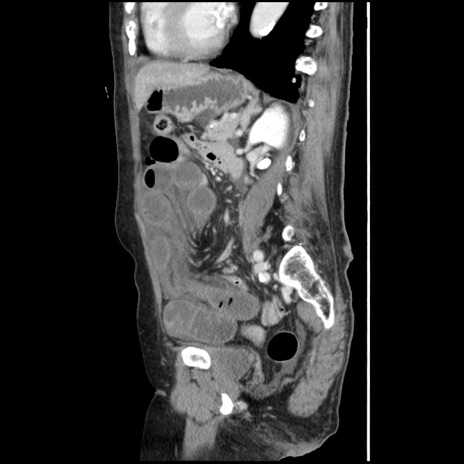

冠状断像

【症例】80歳代女性

【主訴】腹痛

【現病歴】8時間前から腹痛あり来院。

【既往歴】糖尿病、脂質異常症、子宮体癌にて子宮全摘術

【身体所見】意識清明・会話良好だが腹痛で苦悶様、全腹部にわたって反跳痛と圧痛あり

【データ】WBC 13600、CRP 0.14、LDH 224、CK 90